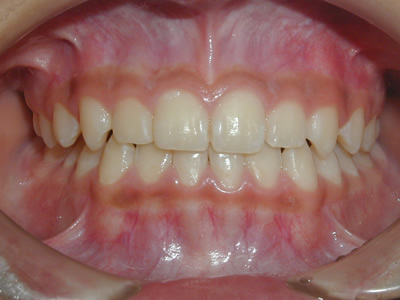

上顎の劣成長 (成長不足) による反対咬合で、上顎は拡大装置と上顎前方牽引装置を併用し前方方向への成長を促して前歯の咬み合わせを改善した後に、上下顎の前歯をマルチブラケット装置で並べました。治療の期間は2年でした。

初診時